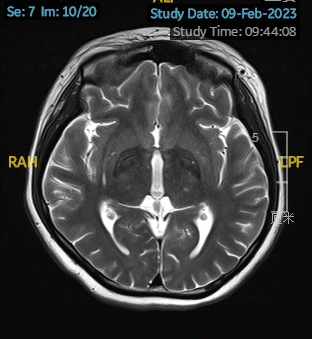

2023.02.09颅脑MR平扫示双侧基底节区及桥脑异常信号,考虑渗透性神经脱髓鞘综合征可能,脑桥部病灶较前范围增大,请结合临床,见图2。

图2 2023.02.09颅脑MR成像示双侧基底节区及桥脑见对称性片样长T1长T2信号,FLAIR呈高信号,较2023-01-18MR所示脑桥病灶范围增大。脑室、脑池、脑沟、脑裂未见明显异常。中线结构居中。